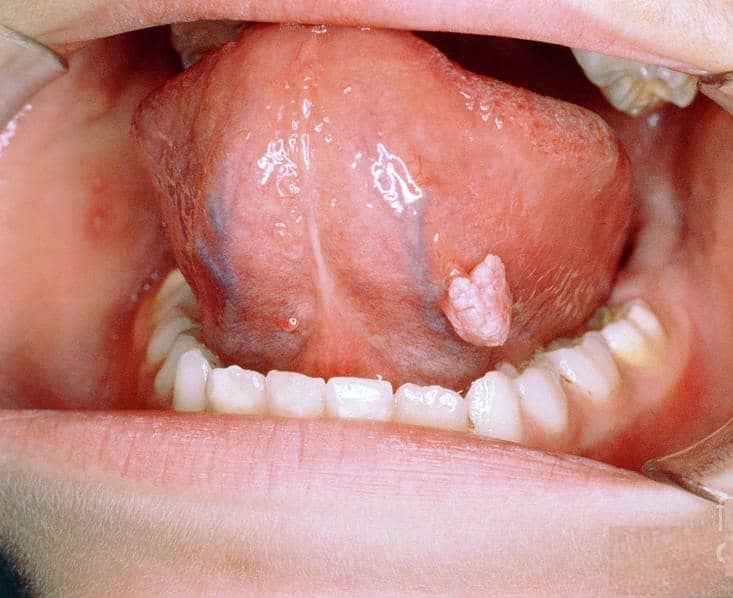

۴- زگیل در دهان (Oral Warts)

زگیل دهانی کمتر شایع است و معمولاً از طریق رابطه جنسی دهانی با فرد مبتلا منتقل میشود.

شکل ظاهری: این زگیلها میتوانند به صورت برجستگیهای کوچک، نرم و بدون درد روی لبها، زبان (به خصوص زیر و کنارههای آن)، سقف دهان (کام) یا داخل گونهها ظاهر شوند. رنگ آنها معمولاً شبیه به رنگ مخاط دهان (صورتی یا سفید) است و ممکن است به صورت منفرد یا خوشهای دیده شوند.